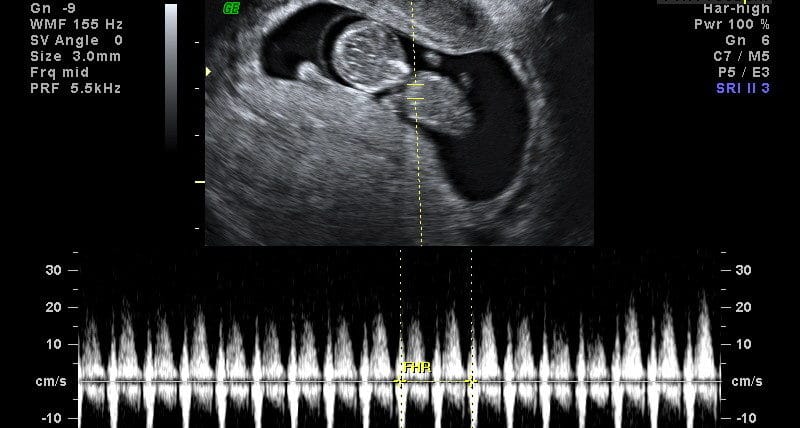

Qual o batimento cardíaco de uma grávida? Um batimento cardíaco acelerado durante a gravidez é acompanhado por muitos outros sintomas, incluindo (12): Do final da 5ª semana até o momento do nascimento, a freqüência cardíaca fetal é medida em cada exame ultrassonográfico. Conheça e saiba como cuidar das alterações com o coração na gravidez. Da mesma forma, a criança sente as carícias e a voz amorosa da mãe e do pai. Se com 6 semanas ainda. Até o início da 9ª semana de gravidez, a. 1.presença de batimentos cardíacos fetais ( bcf ) os batimentos cardíacos fetais podem ser identificados por um aparelho chamado sonar a. Home comunidade gravidez minha primeira gravidez ‿ batimento cardiaco.

Ouvir os batimentos cardíacos de um bebê pela primeira vez é um marco emocionante para os novos pais. Por volta da 5ª semana de gestação, o coração começa a bater e se divide em câmaras. Para identificar a média dessa frequência, os médicos criaram uma tabela da idade gestacional de acordo com o tamanho do feto e tempo de gravidez. Até o início da 9ª semana de gravidez, a frequência cardíaca fetal normal é uma média de 175 bpm. Se o coração bater entre. Alterações hormonais e ganho de peso podem causar taquicardia no início da gravidez. Quanto deve ser a frequência cardíaca na gravidez?. O que é bcf gravidez? Sintomas de batimento cardíaco alto durante a gravidez.